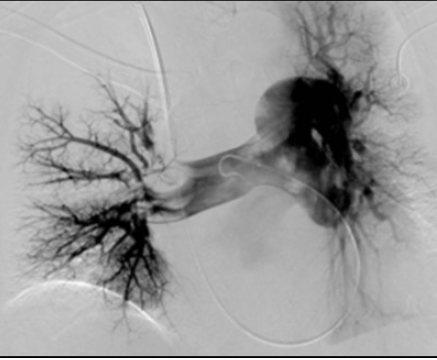

Acute PE

(during angio for thrombolysis)